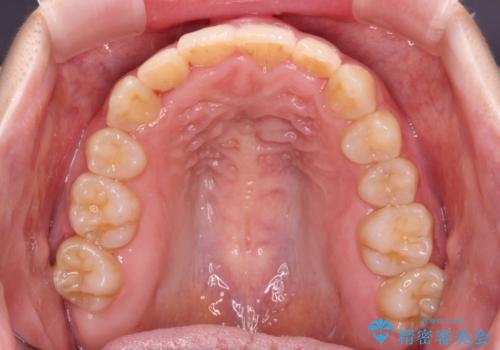

- 右上の八重歯と、左下八重歯を抜いてしまったことを気にして来院された患者様です。

下顎は既に犬歯を1本抜歯しているため、上顎右側第一小臼歯を抜歯し、ワイヤー装置にて歯列を整えることとしました。

変則的な抜歯となるため、正中と人中がずれる可能性がありましたが、仕上がりは上下正中を揃えることができました。